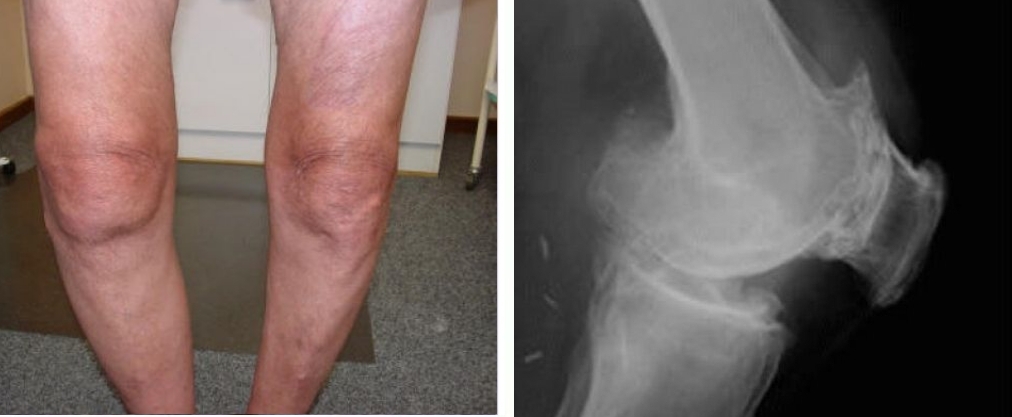

Podívejte se na tyto fotografie. To se stalo těm, kdo příznaky ignorovali. Dnes jsou bezmocní a mnoho z nich nemá na koho se o péči spolehnout. Opravdu chcete takový osud?

Opotřebení kolenních kloubů, závažné pokřivení kolen a neustálá ostrá bolest i při malých pohybech.

Opotřebení a destrukce chrupavky kolen, nekróza tkání, úplná ztráta kloubu a amputace.